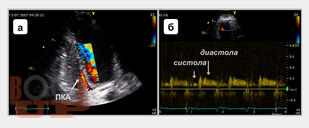

В монографии подробно изложены основные принципы трансторакального ультразвукового исследования магистральных коронарных артерий, включая методические и технические особенности визуализации, обсуждены параметры ламинарного, турбулентного и коллатерального коронарного кровотока, способы оценки и алгоритмы диагностики коронарных стенозов и окклюзий. Также представлены методика определения, способы расчета и критерии оценки резерва коронарного кровотока при трансторакальной допплерографии, показаны диагностическая и прогностическая роли показателя при выявлении гемодинамически значимых коронарных стенозов, окклюзий и определении лечебного эффекта интракоронарных интервенционных вмешательств. Книга рассчитана на кардиологов, врачей функциональной и ультразвуковой диагностики, эндоваскулярных хирургов, патофизиологов, студентов медицинских вузов.